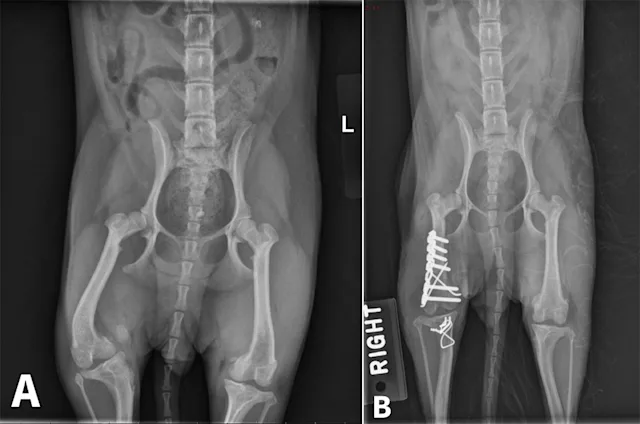

Image Gallery: Angular Deformities

Angular limb deformities (ALD) can occur in both small and large companion animals and can result in significant functional impairment. Although any long bone in dogs can be affected, ALD are most commonly seen in the antebrachium, as well as in the femur and tibia secondary to patellar luxation.1 Deformities may develop secondary to abnormalities in bone growth (eg, premature closure of physis following trauma), bone formation (eg, disease process disrupting normal endochondral ossification; hypertrophic osteodystrophy, retained cartilaginous core, nutritional disorders), or bone healing (eg, fracture malunion).

Figure 1. Radial valgus and external torsion.